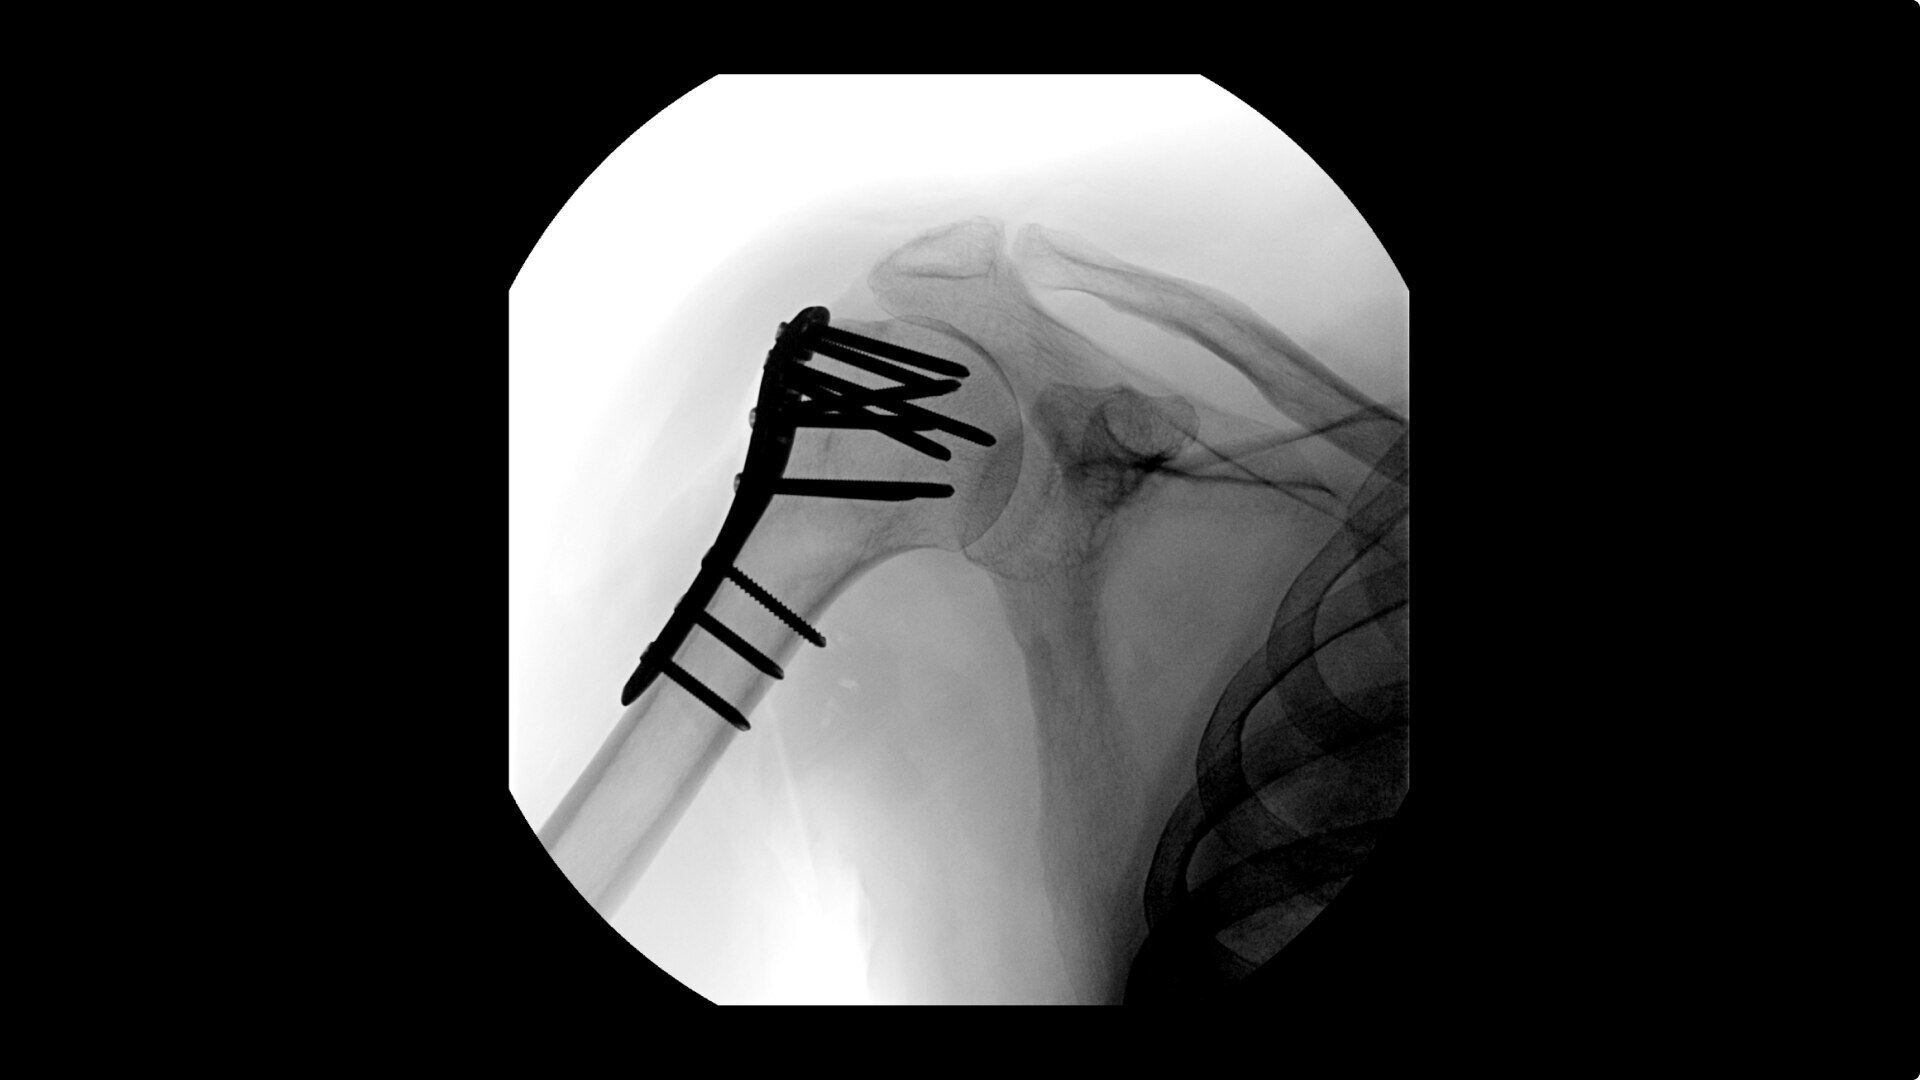

OEC C-arms provide orthopedic imaging with a large field of view optimized to clearly visualize orthopedic anatomy, such as the entire long bone femur or minute fractures in extremities. A clear display with comfortable viewing can easily show AP and lateral views, enabling efficient procedure planning.

Complex orthopedic procedures require powerful imaging systems. OEC premium C-arms perform in a variety of procedures such as:

• Humeral fracture

• Shoulder fracture reduction